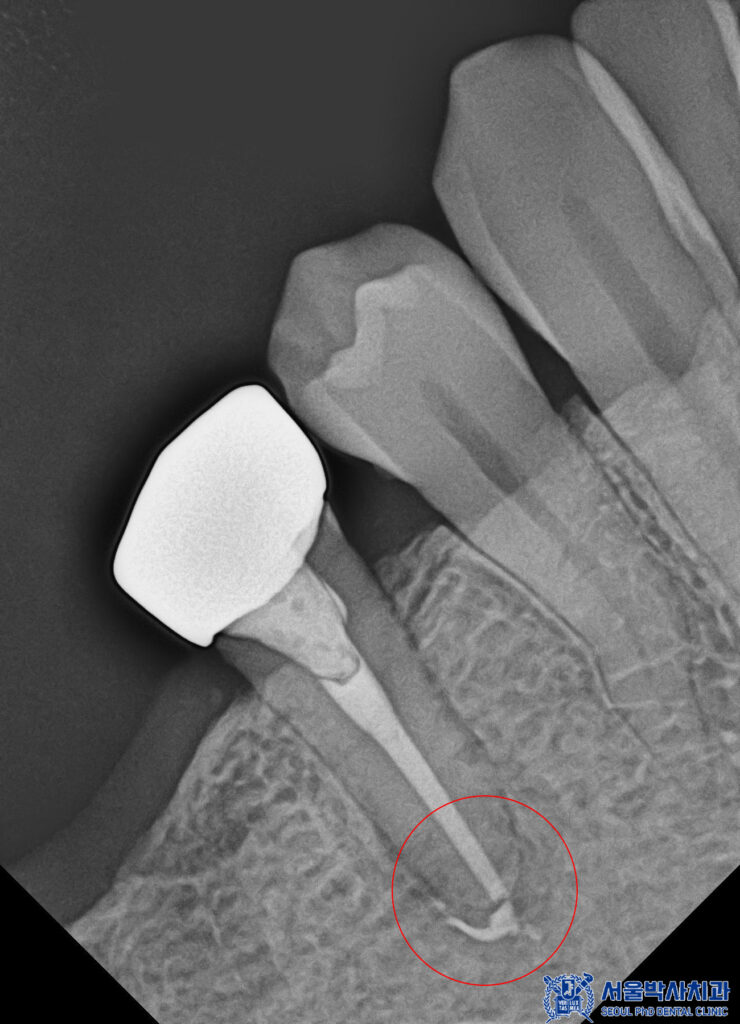

이렇게 기존의 재료들을 제거하고

재신경치료를 진행하였습니다.

신경치료를 마무리한 후에는

치아 내부를 안정적으로

보강하는 과정이 필요합니다.

레진을 이용하여

치아의 빈 공간을 채워주었습니다.

이는 약해진 치아에 강도를 보완하고

이후 보철물이 안정적으로

자리 잡을 수 있도록 돕는

중요한 단계입니다.

치료 후 엑스레이 촬영을 통해

확인한 결과,

뿌리 끝 염증이 이전보다

눈에 띄게 감소한 것을

확인할 수 있었습니다.